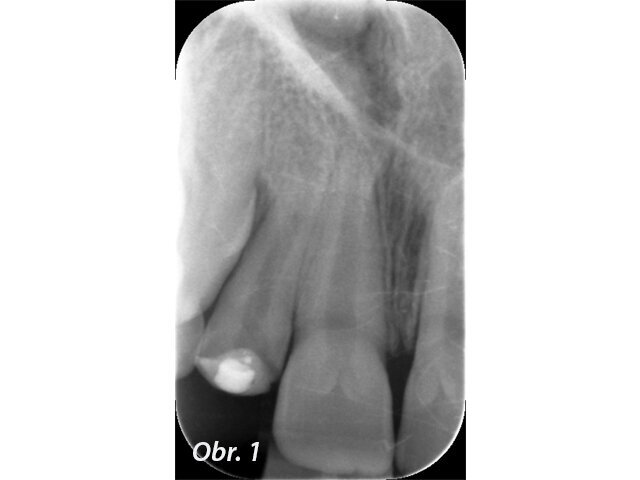

Prvním možným řešením je umístění MTA přímo do dekontaminovaného apexu zubu. U kratších rovných kořenů jde se správným instrumentáriem o poměrně snadný výkon. V případě 12letého chlapce referovaného po fraktuře zubu šlo ale o postranní řezák 12 s výrazným apikálním zahnutím, kam bylo s rigidní zahnutou koncovkou tzv. „MTA gun“ v roce 2011 nemožné aplikovat dostatečně hluboko. V dnešní době s flexibilními koncovkami MAP systému by zřejmě tento problém neexistoval. Přestože nebyl zub zcela zaplněn, předchozí dekontaminace a potentní dětská tkáň zajistily, že se veškerý zbývající prostor kořene vyplnil zřejmě dentinoidní tkání. Zub byl opatřen adhezivní dostavbou s FRC čepem a pryskyřičnou korunkou. (Obr. 1–3)

Popsané řešení má výbornou prognózu.